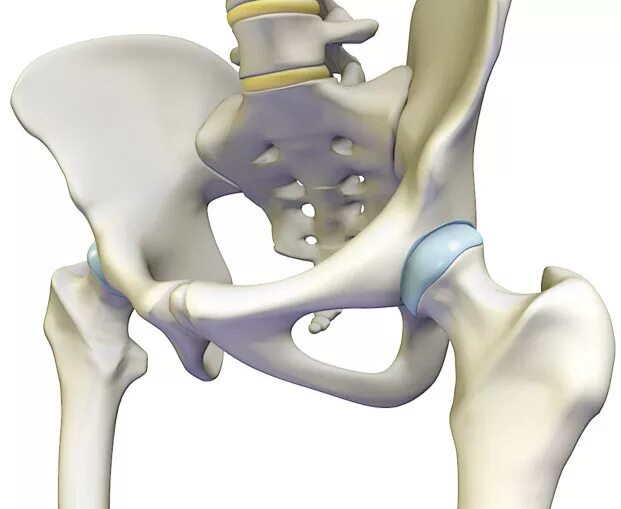

Тазобедренный сустав это